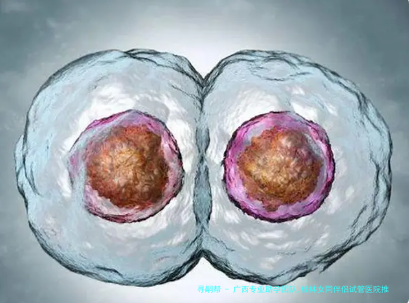

广西专业助孕团队的突出长处在于其技术整合能力。他们一般来说配备由生殖NF专家、胚胎专家和遗传生物学顾问构成的跨学术领域集体,能够针对不同家庭需求计划精确的助孕路径。例如,至于卵巢机能衰退或存留遗传性疾病史的夫妻,团队会综合采用体外受精(试管婴儿)、卵细胞质内单精子注射(显微受精技术)等技术,并结合胚胎植入前基因学检测(PGT),筛查出优质胚胎进行移植。这一类多技术调和模式,将临床妊娠率提升至60%以上。

基因筛查技术的运用,是保障新生儿健康的核心防卫线。广西专业团队普遍采用三种筛选:

PGT-A(胚胎染色体检查筛选):肃清非整倍体胚胎,降低早产风险;

PGT-M(单基因为疾病筛选):针对地中海贫血、囊性纤维化等遗传性疾病,阻隔导致疾病基因传递;

携带体筛查:对夫妇两边进行隐性遗传病基因检测,评估胚胎抱病概率。

技术水平面,高通量测序(NGS)使筛查准确程度达95%上述。例如,对染色体异常的胚胎识别率接近百分之九十九,可避免70%之上的遗传性疾病。